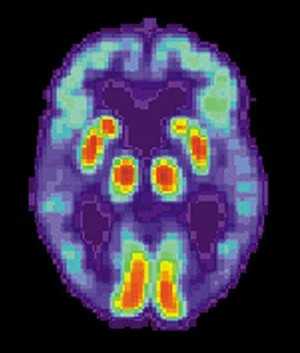

A descoberta da primeira substância química capaz de prevenir a morte do tecido cerebral em uma doença que causa degeneração dos neurônios foi aclamada como um momento histórico e empolgante para o esforço científico.

Ainda é necessário maior investigação para desenvolver uma droga que possa ser usada por doentes. Mas os cientistas dizem que um medicamento feito a partir da substância poderia tratar doenças como Alzheimer, Mal de Parkinson, Doença de Huntington, entre outras.

Em testes feitos com camundongos, a Universidade de Leicester, na Grã-Bretanha, mostrou que a substância pode prevenir a morte das células cerebrais causada por doenças priônicas, que podem atingir o sistema nervoso tanto de humanos como de animais.